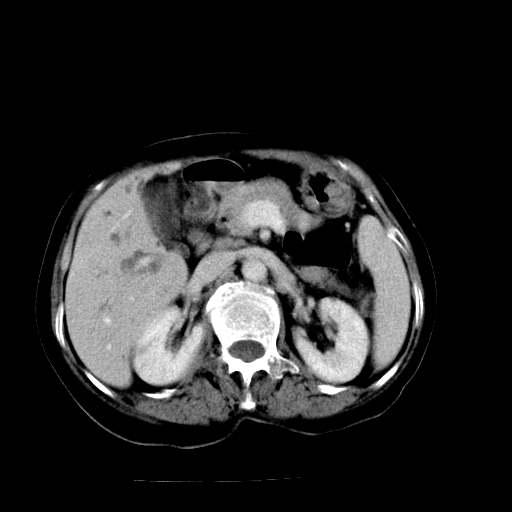

以下是引用卜一在2009-4-7 5:06:00的发言:[br]左右肝内胆管结石伴扩张合并胆系感染;不除外胆管细胞癌可能。支持! [br] [br]